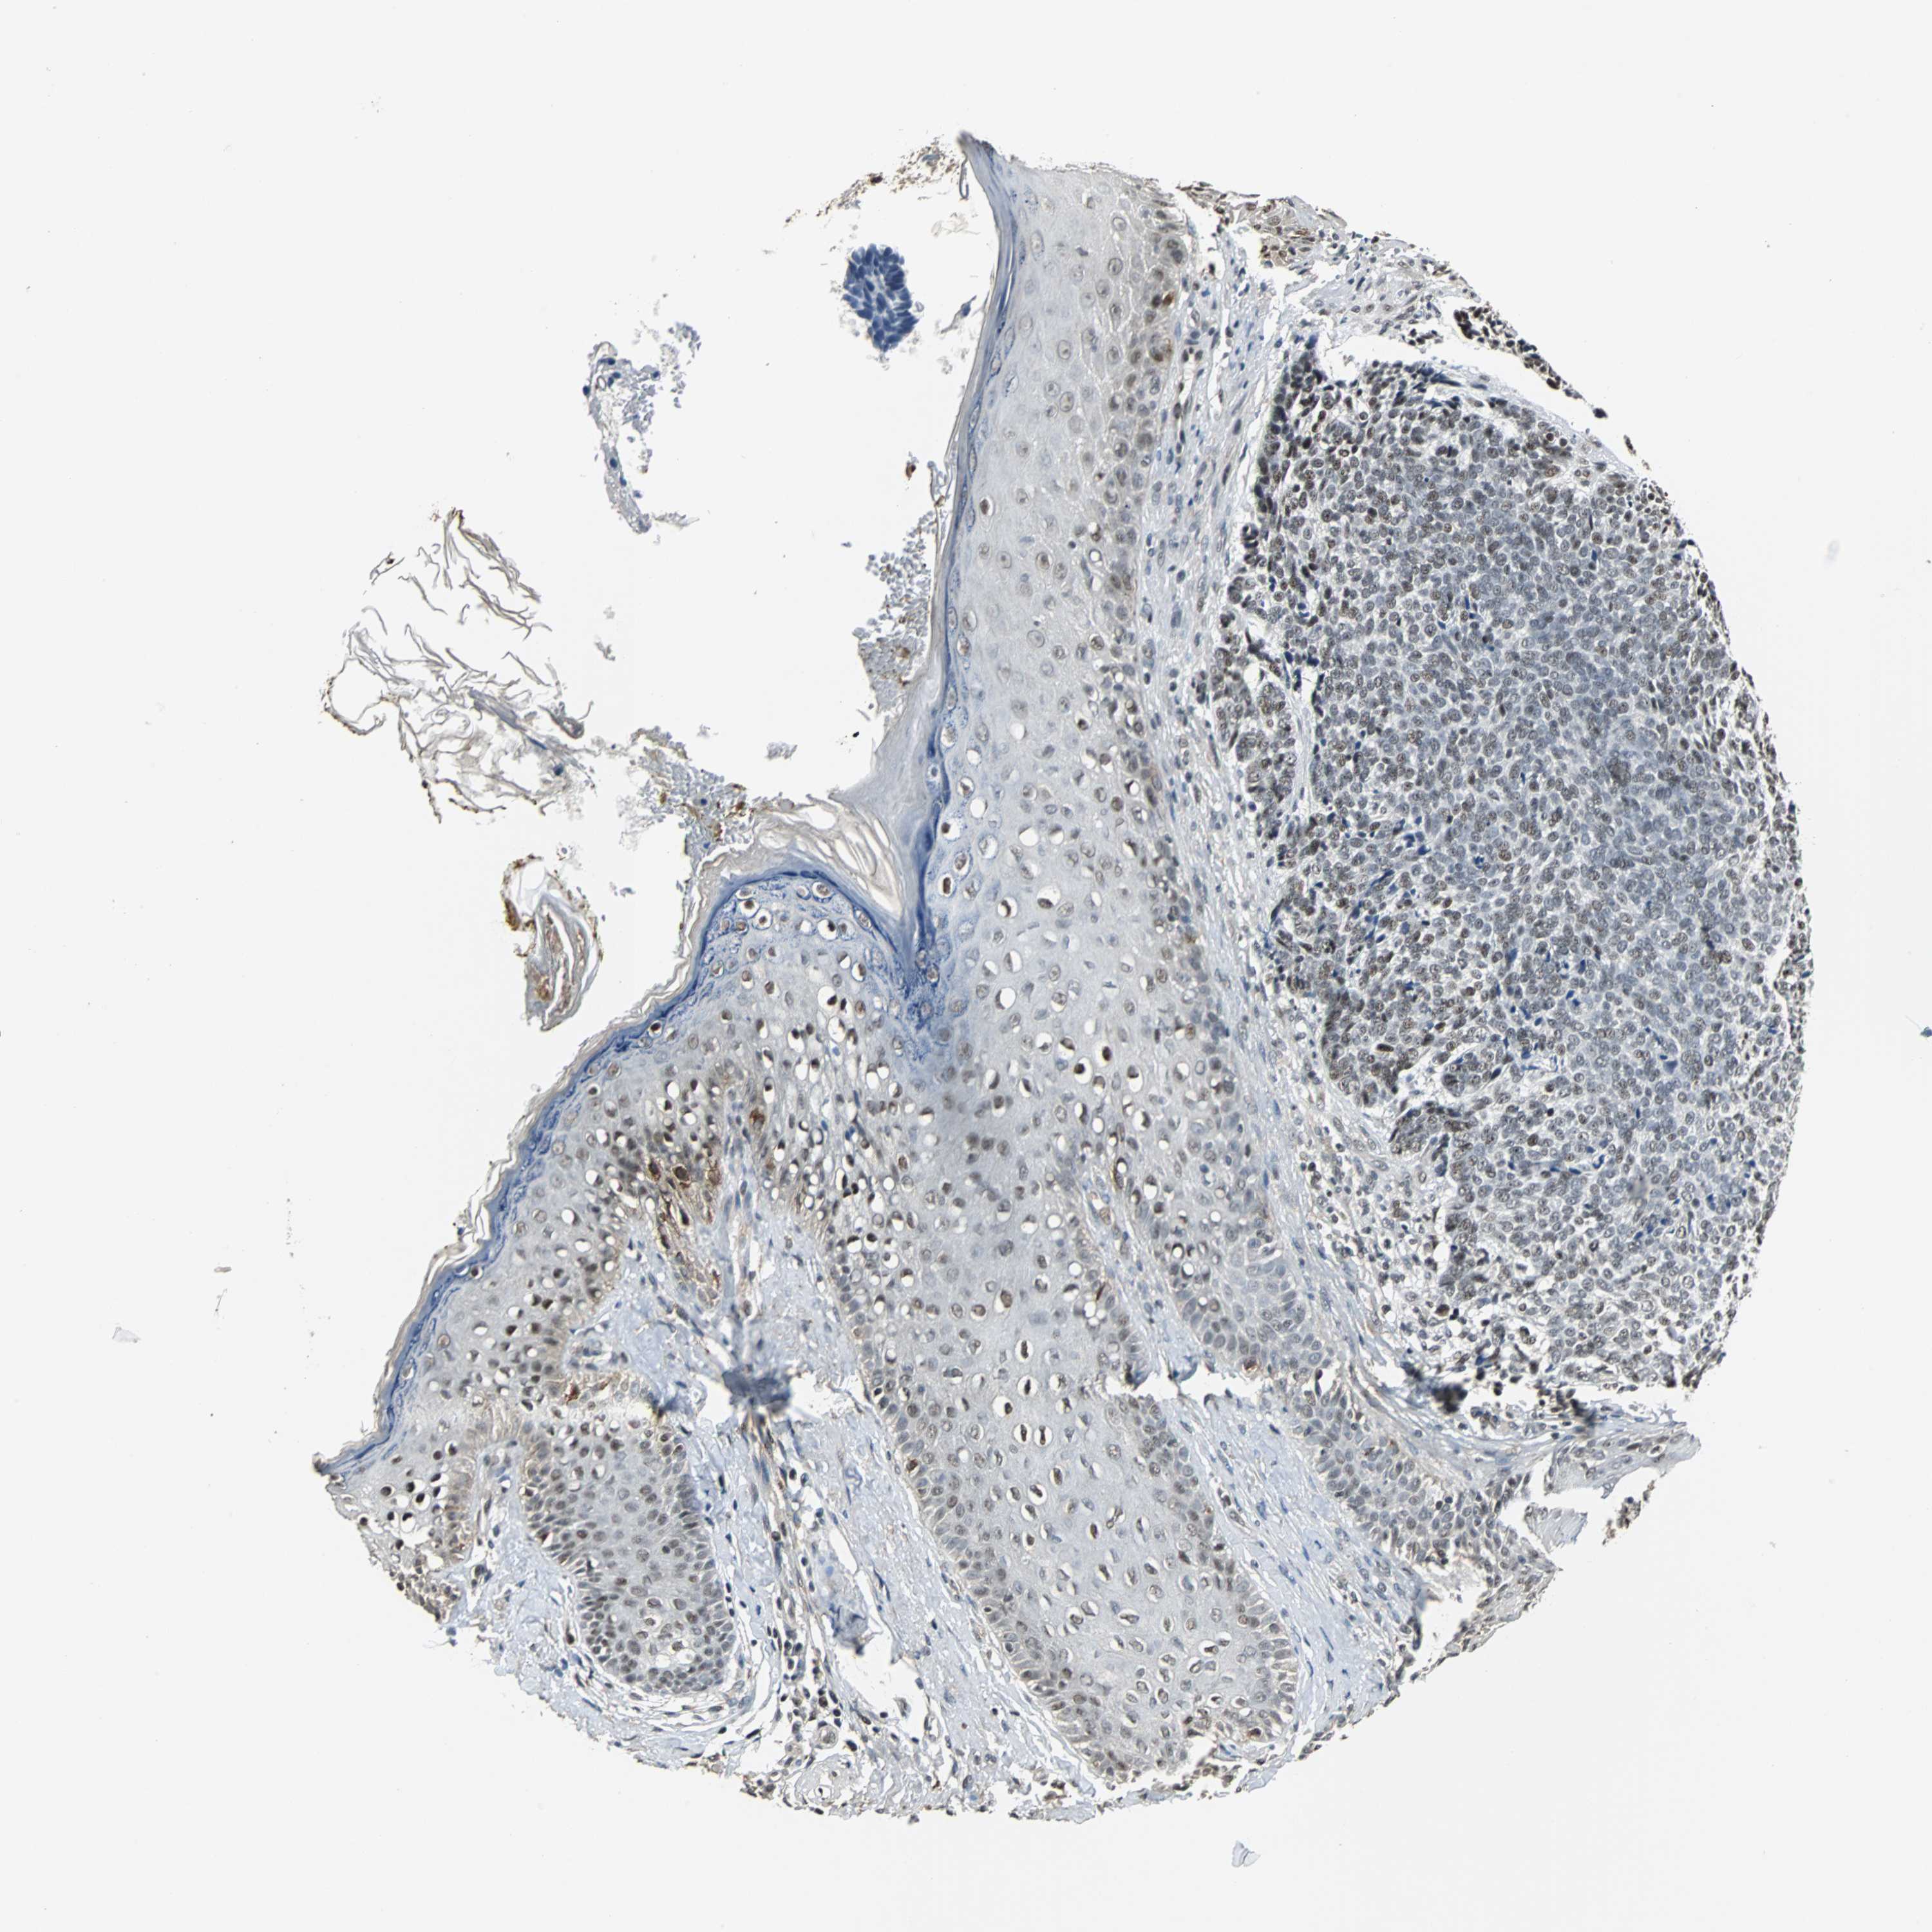

SKIN CANCER - Protein expressioni

A mouse-over function shows sample information and annotation data. Click on an image to view it in a full screen mode. Samples can be filtered based on level of antibody staining by selecting one or several of the following categories: high, medium, low and not detected. The assay and annotation is described here.

Antibody staining in the annotated cell types in the current human tissue is reported as not detected, low, medium, or high, based on conventional immunohistochemistry profiling in selected tissues. This score is based on the combination of the staining intensity and fraction of stained cells.

Each image is clickable and will lead to virtual microscopy that enables deeper exploration of all samples and also displays staining intensity scores, fraction scores and subcellular localization as well as patient and tissue information for each sample.

Antibody HPA006232

Staining

High

Strong

Quantity

Location

Squamous cell carcinoma, NOS